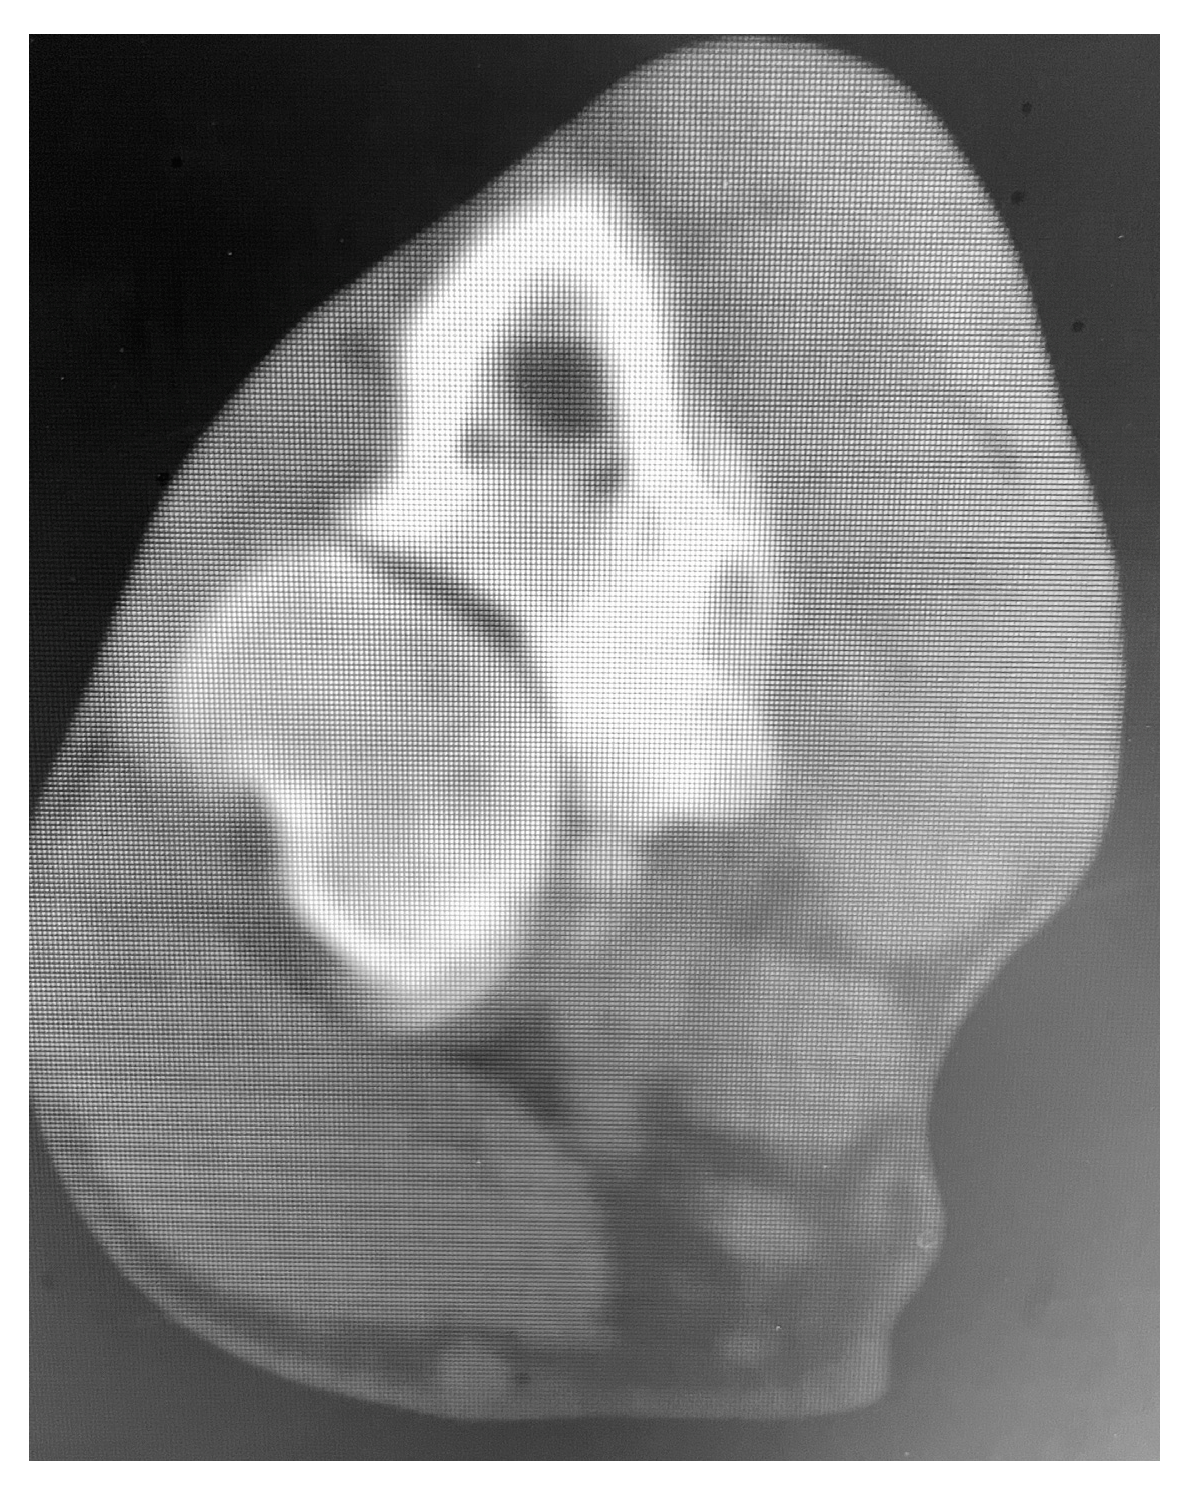

The dogs were selected for SHO based on poor or no response to conservative treatment. Lameness score, history, and preoperative imaging findings were recorded. All dogs presented varying degrees of lameness (three dogs’ grade 2 lameness and two dogs’ grade 3 lameness). Exacerbation of clinical signs with exercise was reported by all owners. All dogs presented the elbow slightly abducted and the antebrachium and manus in slightly external rotation. Orthopedic examination elicited a pain response on manipulation and palpation of the elbow joint in all dogs. Pain was obvious during deep palpation of the medial compartment of the joint, close to the tendon of insertion of the biceps brachii muscle. Flexion of the joint and supination of the distal limb induced a pain response also in all dogs. Joint effusion was palpated in three dogs (cases 1, 3, and 5). Enlargement of the joint, decreased range of motion, and crepitation was palpated in dogs 2 and 4 as the disease was more chronic. History and positive results of clinical and orthopedic examination highly raised suspicion for medial compartment elbow disease, and a CT scan (Siemens Emotion 1.25 mm slice) was performed for all dogs (Figure 1).

Figure 1. CT image of case 1 treated with MCDE. Note the small and misshapen medial coronoid process with decreased density and separated from the adjacent bone.